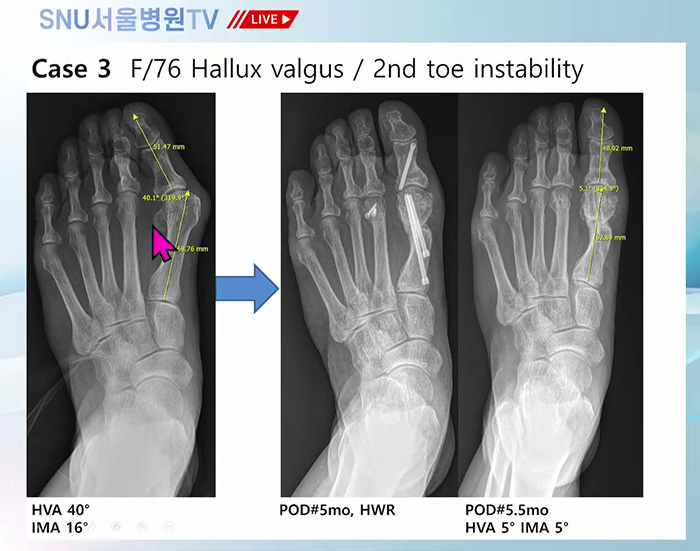

족부전담팀 강태병 원장님께서 직접 집도했던 최소침습 무지외반증 수술, MITA 수술 사례를 직접 보여주며 설명해 주셨는데요!